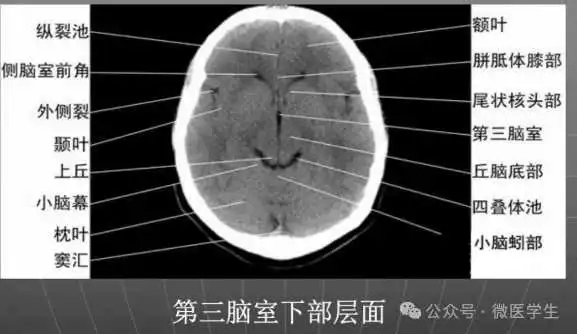

显示侧脑室前角的下部:

- 前方---额叶;外侧---尾状核头部;后方中线处---第三脑室,其两侧连接丘脑。

颅后窝:

- “Y”字形或“V”字形的小脑幕,幕下结构在内侧(小脑上蚓部),幕上结构在外侧(枕叶)。

四叠体池:

- 位于小脑蚓部前方。